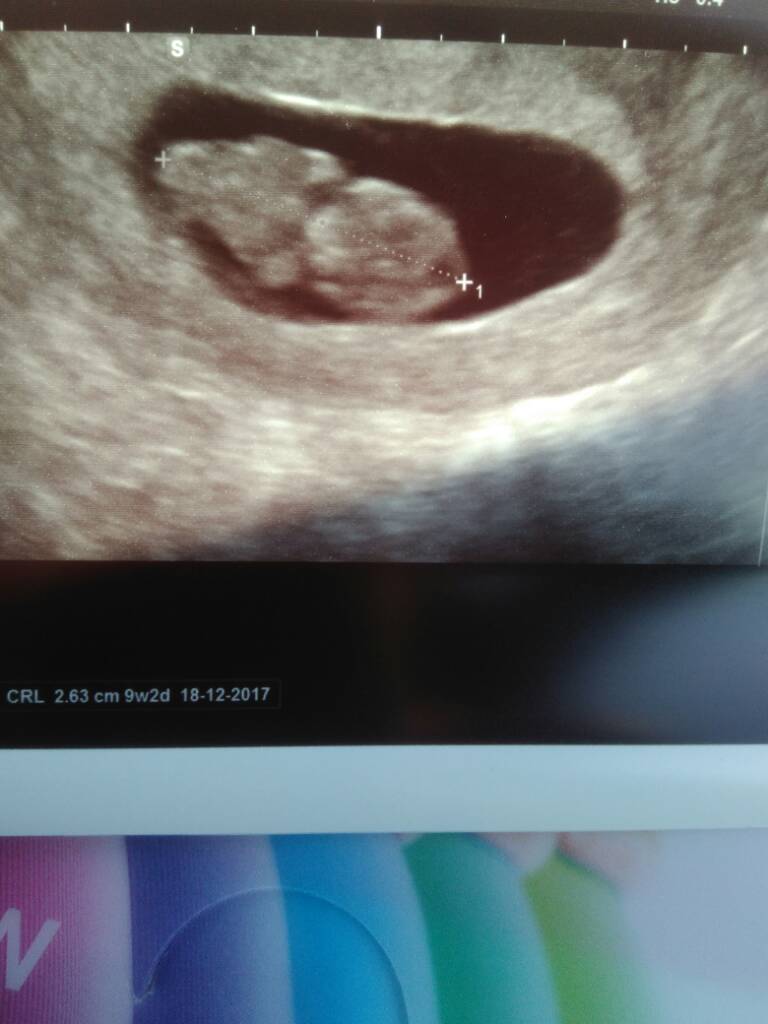

<3 cudeńkoZobacz załącznik 806915

Mój maluszek według OM 9w6d według USG 9w2d